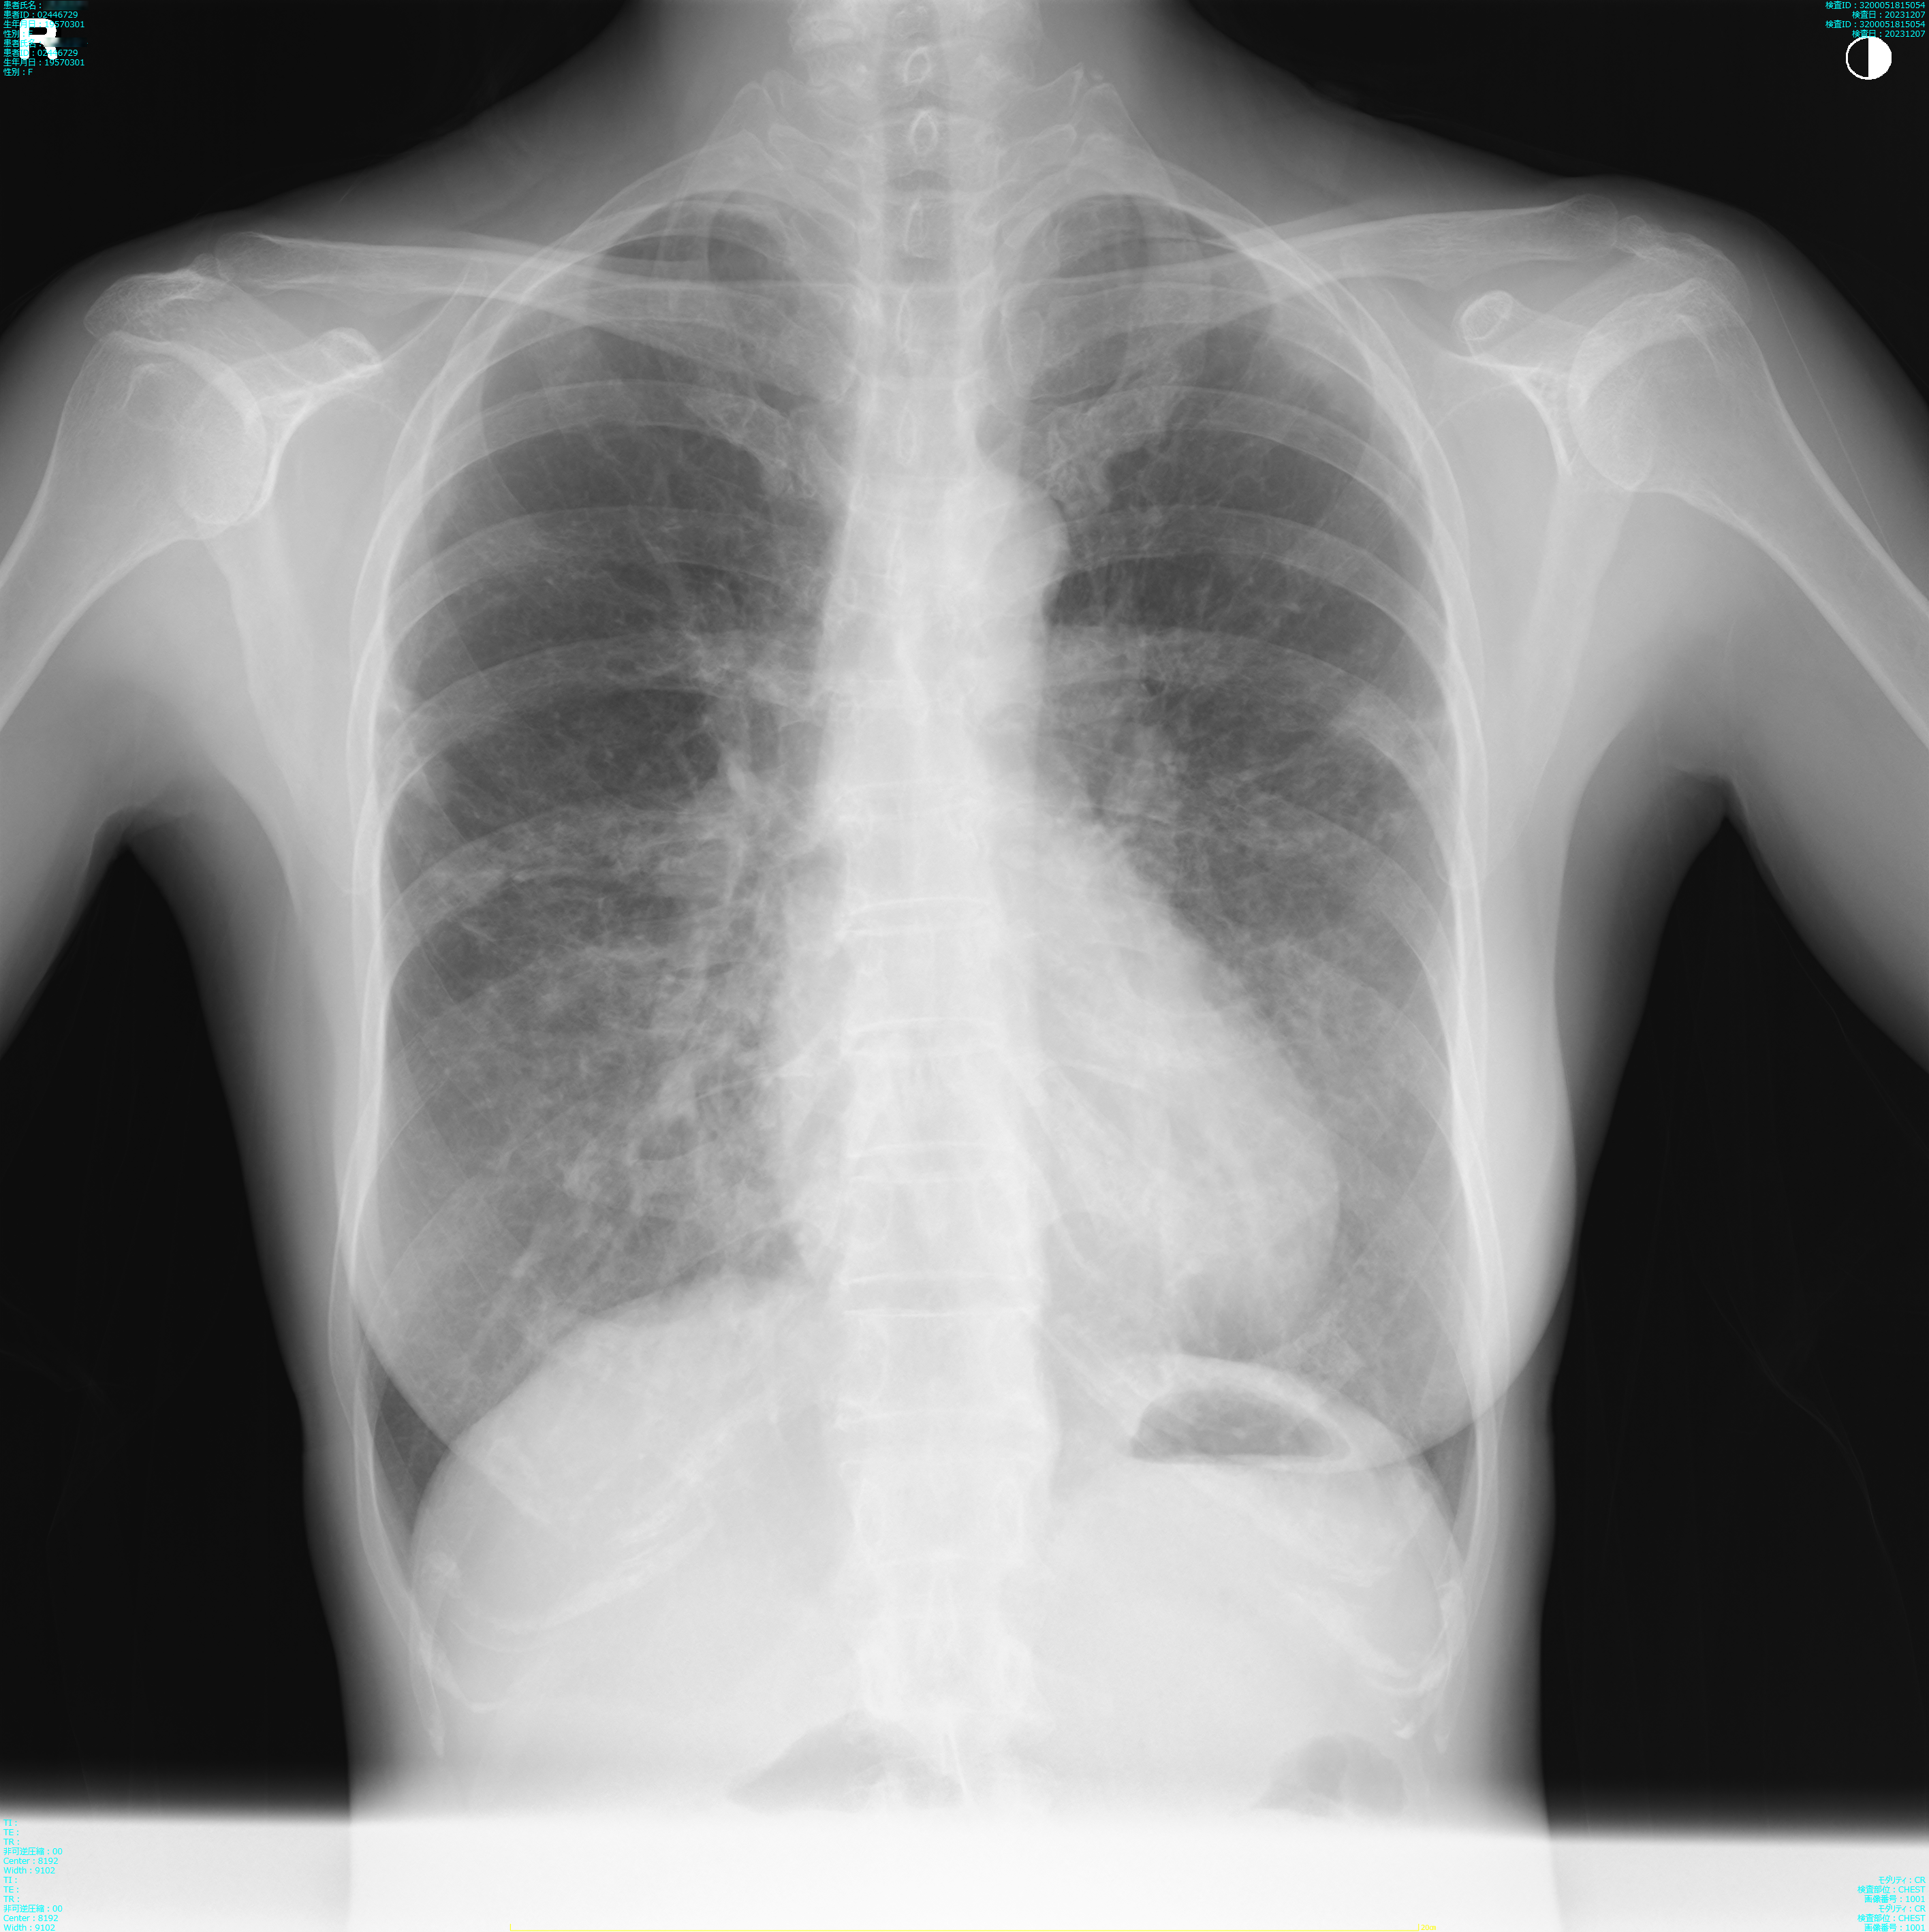

- 2023.12.07 入院前の画像(国立系病院)